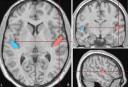

"Diferencias en las estructuras cerebrales bilingües"![]() 28/11/12. Fuente: Universitat Pompeu Fabra. Estudio publicado el 21/nov/12, en The Journal of Neuroscience, por investigadores del Centro de Cognición y Cerebro del DTIC y dirigido por Núria Sebastian, de la Universitat Pompeu Fabra. |